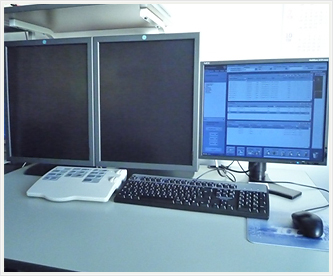

Seno Advantage Workstation

当院では、撮影後上図のワークステーションというモニターに画像が転送されます。患者様も画像を見ながら、医師の説明を受 けることができます。